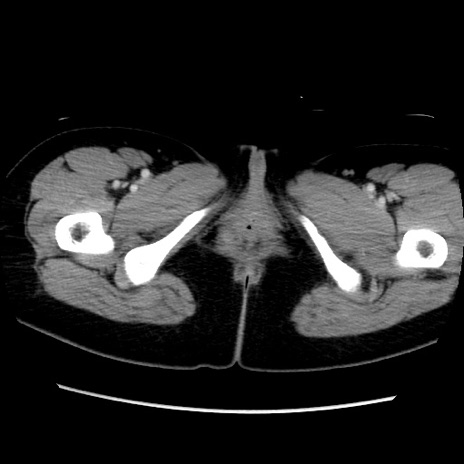

症例39(横断像)

【症例】40歳代女性

【主訴】上下腹部痛

【現病歴】2日目から下腹部痛あり。夜間は痛みで眠れなかった。昨日より上腹部痛と下痢が出現。臥位で痛みは軽快したため、休んでいた。本日になって臥位でも立位でも痛みが強くなってきたため救急要請。

【既往歴】子宮内膜症

【身体所見】部:平坦・軟、左上下腹部に圧痛あり、反跳痛あり。

【データ】WBC 21800、CRP 26.78